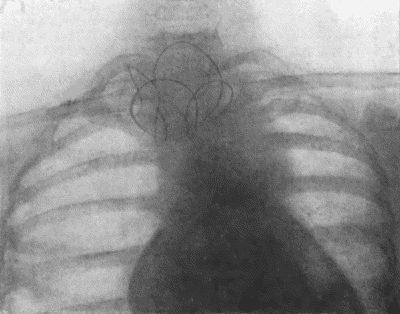

73.Radiogram of Innominate Aneurysm after Treatment by Moore-Corradi method 309